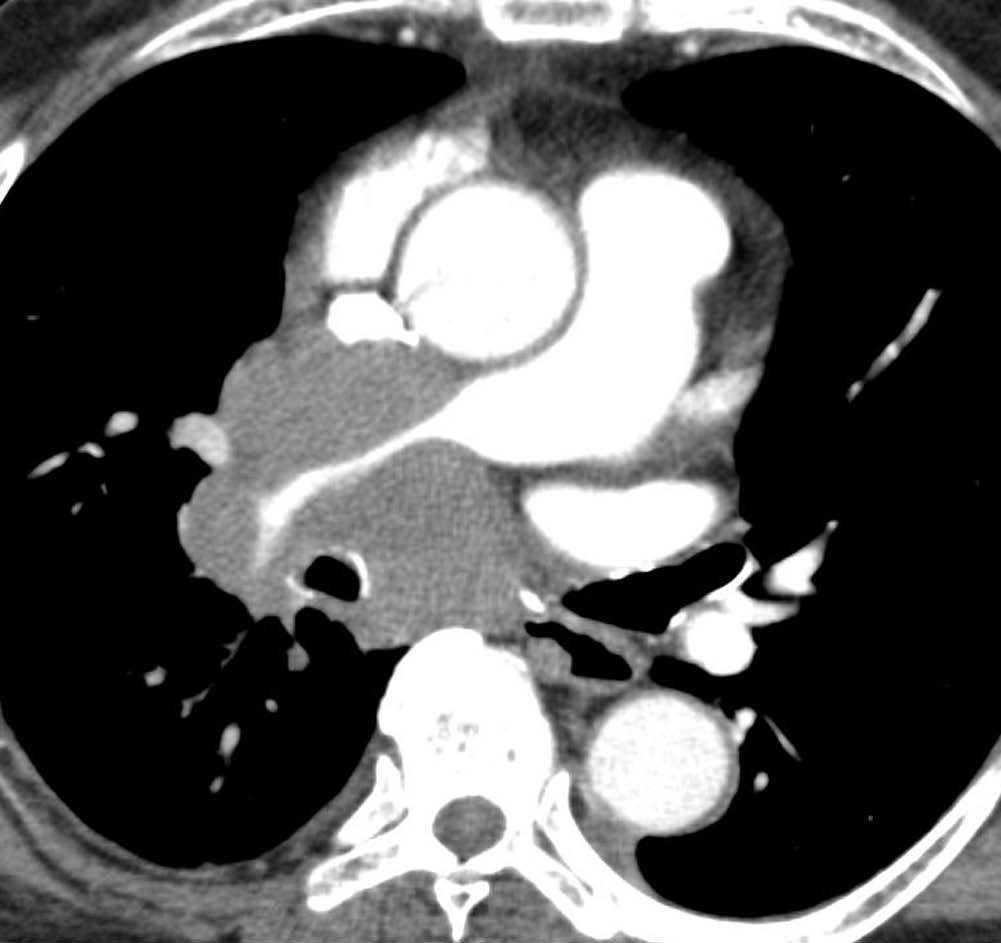

El estadio tumoral (T) se basa en el tamaño, localización y relación con las estructuras adyacentes valorado mediante TC. Los tumores T1 son aquellos de 3 cm o menores en su diámetro mayor, rodeados de pulmón y que no invaden la pleura visceral ni los bronquios principales, mientras que los T2 son lesiones mayores de 3 cm, o aquellas que invaden la pleura visceral o al bronquio principal a más de 2 cm de la carina o que condicionan atelectasia o neumonitis obstructiva que no afecte a todo el pulmón. La diferenciación entre ambos estadios tumorales suele ser sencilla mediante TC, salvo la afectación de la pleura visceral, aunque esta no tiene un impacto importante en el manejo clínico. El tumor T3 viene determinado por la infiltración de estructuras vecinas potencialmente resecables, como la pared torácica, diafragma, pleura mediastínica, pericardio parietal o si el tumor está situado a menos de 2 cm de la carina (fig. 1). Los tumores T4 son aquellos que no pueden ser resecados porque engloban a estructuras vitales, invaden el corazón, grandes vasos, esófago o cuerpos vertebrales (fig. 2) o en los que existe un nódulo o nódulos en el mismo lóbulo del tumor. Además de definir la T, es importante reflejar las particularidades de la infiltración de estructuras en vecindad que puedan modificar la actitud terapéutica. Por ejemplo, cambiará la estrategia quirúrgica según el tipo de bronquio afecto o la estructura mediastínica infiltrada, si es sólo la grasa, o un vaso; cuando existe neumonitis o atelectasia secundaria a un tumor central, la planificación del campo de radioterapia dependerá del límite entre la masa y la repercusión pulmonar.

Fig. 2.--T4. (A) Corte axial de tomografía computarizada (TC) torácica con contraste. Tumor hiliar derecho que infiltra la arteria pulmonar derecha, la vena cava superior y engloba al bronquio intermediario. (B) Reconstrucción coronal oblicua, longitudinal al eje de la arteria pulmonar derecha, que muestra cómo engloba el tumor a la rama del truncus superior (flecha blanca) e inferior (flecha negra).